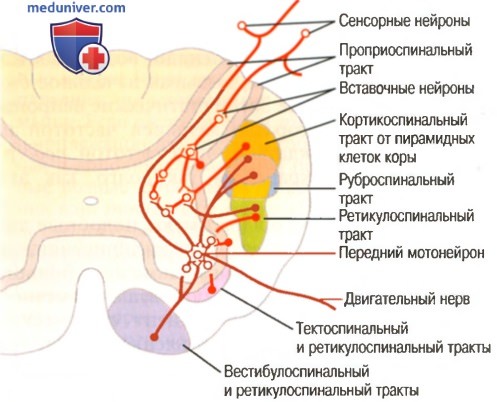

Пирамидная симптоматика в неврологии: ключевые аспекты